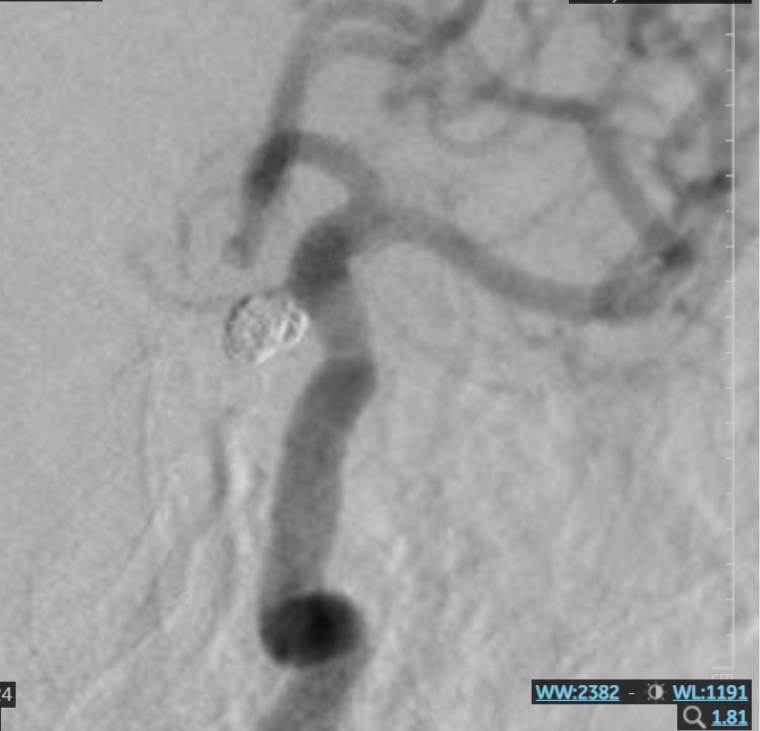

Hình ảnh túi phình mạch máu não sau can thiệp

Can thiệp nội mạch nút túi phình bằng coil là phương pháp ít xâm lấn, sử dụng ống thông luồn từ mạch máu ngoại vi lên đến não, tiếp cận túi phình. Sau đó, đưa các vòng xoắn kim loại cực nhỏ (coil) vào bên trong túi phình. Các coil này sẽ chặn dòng máu vào túi phình, từ đó “bịt kín” túi phình và ngăn ngừa nguy cơ vỡ túi phình, bảo tồn mạch máu. Can thiệp nội mạch nút túi phình bằng coil là phương pháp đã được đánh giá là hiệu quả, được áp dụng tại nhiều cơ sở y tế, mang lại lợi ích cho người bệnh như:

BS. Lục Đình Phương – Khoa Sọ Não Cột Sống 2 Bệnh viện Đa khoa Xuyên Á cho biết: “Ca can thiệp này tương đối phức tạp. Túi phình của bệnh nhân có kích thước tương đối lớn, cổ túi phình khá rộng, lại nằm ở góc khuất – góc đảo ngược của dòng chảy mạch máu, gây khó khăn trong việc chọn lọc đưa ống thông vào và đặt coil can thiệp chính xác. Dù vậy, với kinh nghiệm và kỹ năng chuyên môn, ekip bác sĩ đã can thiệp thành công, loại bỏ hoàn toàn túi phình, không để lại biến chứng thần kinh.”

Sau can thiệp, sức khỏe bệnh nhân ổn định và đặc biệt là tình trạng đau đầu đã biến mất. Hiện tại, bệnh nhân đã xuất viện và sẽ tiếp tục điều trị thoát vị đĩa đệm trong thời gian tới. Sau khi xuất viện, người bệnh cần kiểm soát chặt chẽ bệnh lý tăng huyết áp nhằm giảm áp lực lên thành mạch, phòng ngừa túi phình tái phát hoặc vỡ lại.